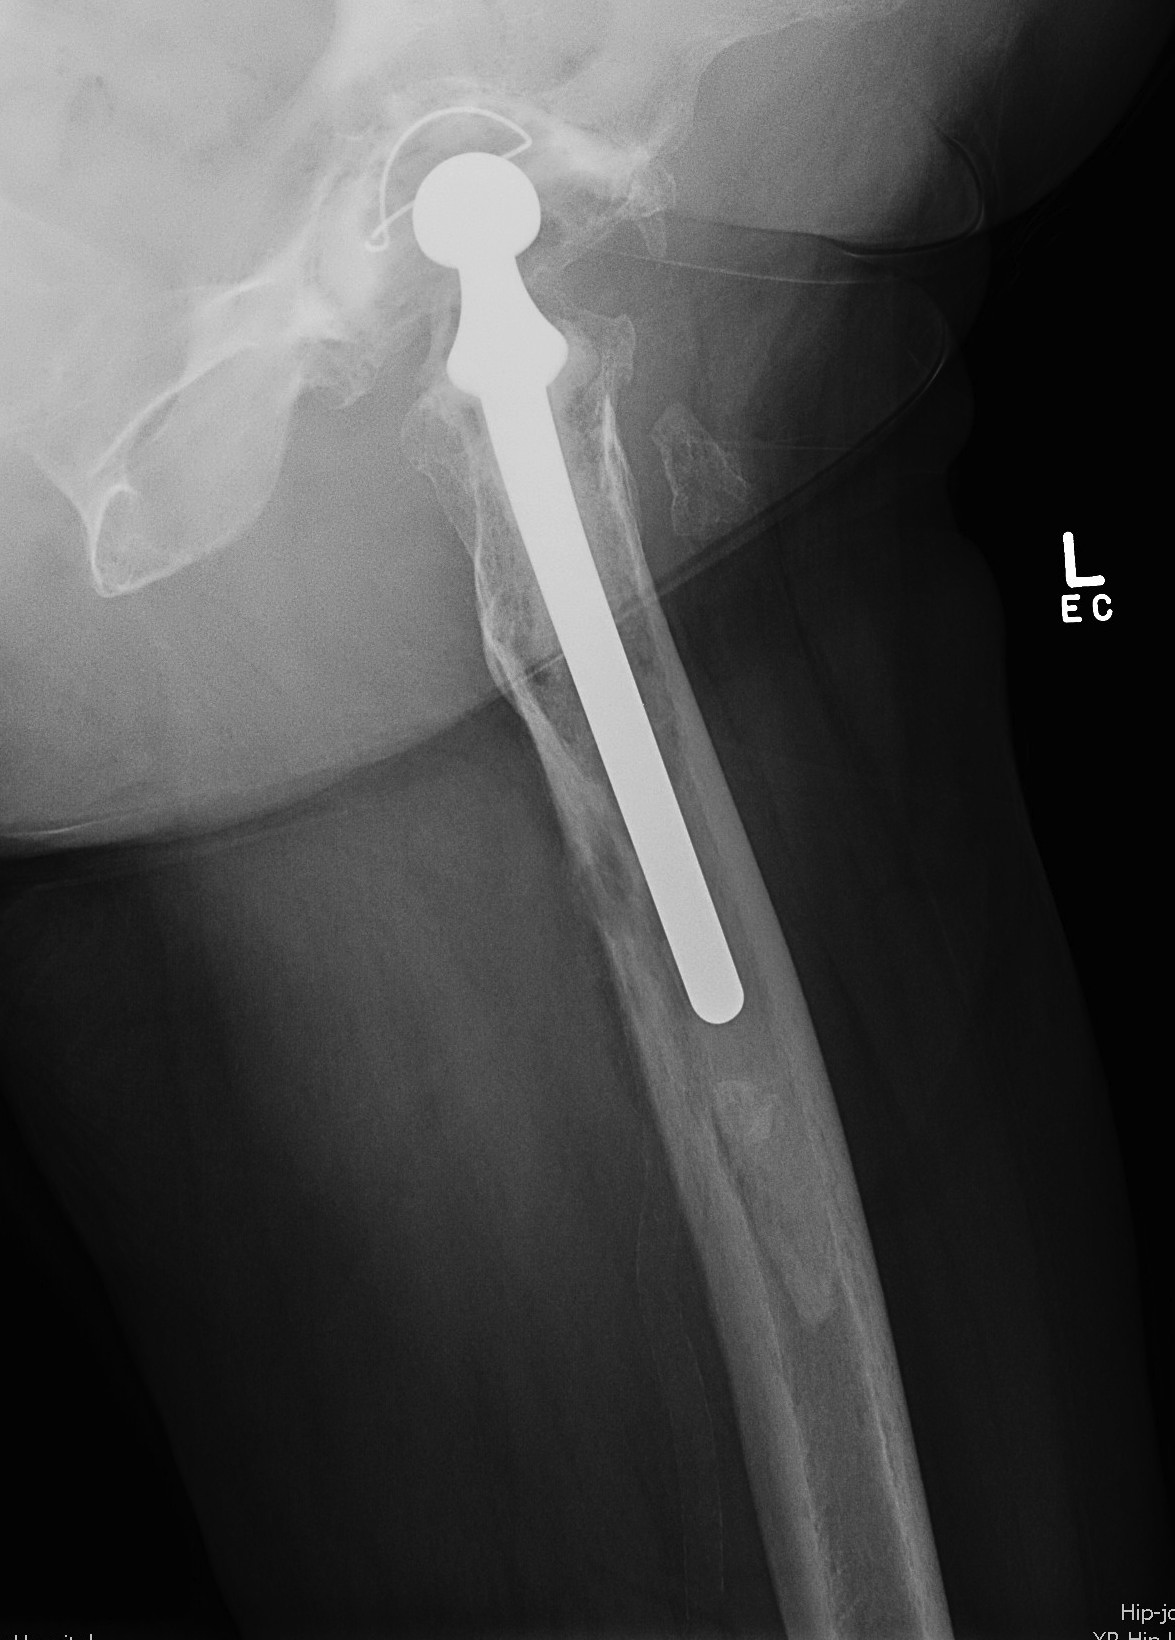

IIIB Metaphysis severely damaged / < 4cm diaphyseal bone for distal fixation

- cemented with cement restrictor

- uncemented with substantial distal osteolysis

IV Extensive metaphyseal and diaphyseal bone loss / isthmus non supportive